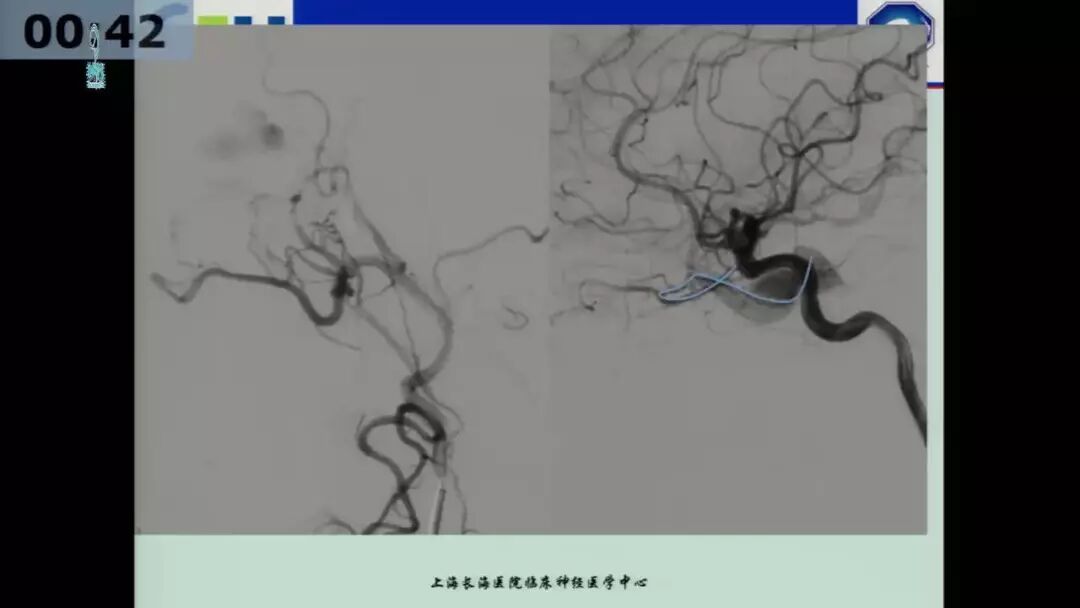

今天为大家分享的是由海军军医大学附属长海医院许奕教授在四川省医学会第十二次介入医学学术暨西南神经介入高峰会议上带来的“海绵窦区脑膜动静脉瘘的介入治疗”精彩讲课视频和PPT,欢迎观看!(内容未经讲者审核,不当之处请与我们联系)

许奕教授:海绵窦区脑膜动静脉瘘的介入治疗